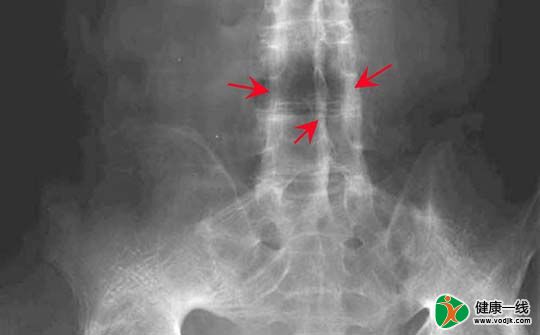

晨起腰背痛别当腰病治,可能是强直